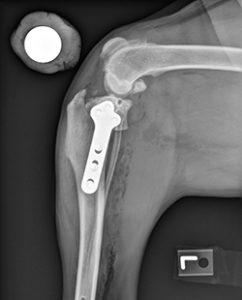

Tibial plateau leveling osteotomy (TPLO)

Tibial plateau leveling osteotomy (TPLO) involves making a circular cut in the tibial plateau and rotating the contact surface of this bone until it attains a relatively level orientation that puts it at approximately 90 degrees to the attachment of the quadriceps muscles (see Figure 2). This orientation of the tibial plateau renders the knee relatively stable, independent of the CCL. The cut in the bone needs to be stabilized by the use of a bridging bone plate and screws. Once the bone has healed, the bone plate and screws are not needed, but are seldom removed unless there is an associated problem. The greatest advantage of this technique is the perceived superior outcome (limb function and less progression of arthritis) compared to traditional suture techniques especially in young, large breed dogs. The major disadvantage is the need to perform an osteotomy. Any osteotomy requires healing of the bone and if a problem is observed (such as implant failure, failure of the bone to heal), it may require multiple revision surgeries and the outcome may be poor. Luckily, such complications are rare, especially when the procedure is performed by an experienced surgeon.